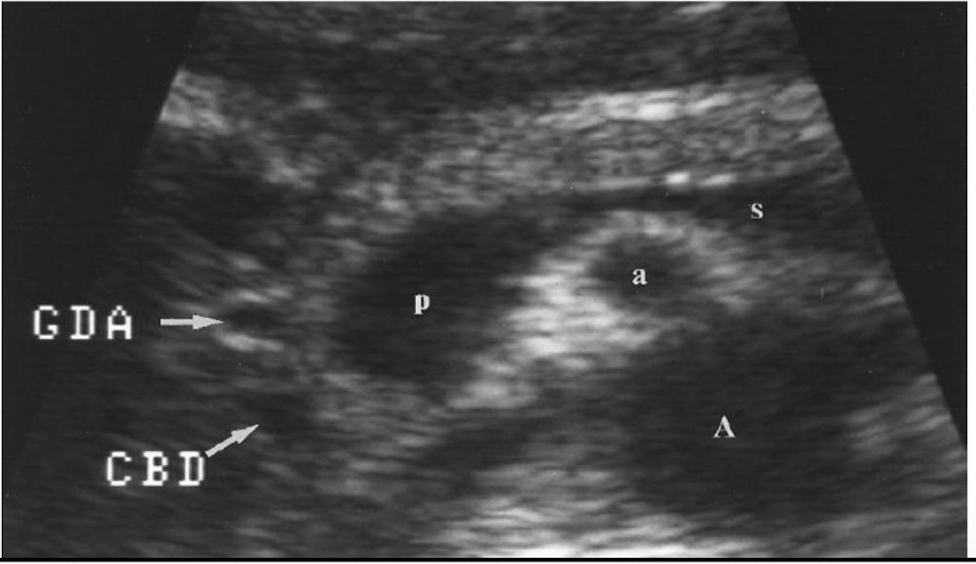

Be able to identify this image taken in a transverse plane

Which round anechoic structures can be visualized within the pancreatic head

Gastroduodenal artery (GDA) & Common Bile Duct (CBD)

Usually within the pancreatic head the gastroduodenal artery is ___(1)________ and the common bile duct is _____(2)______. But, if you are unsure which is which what is an easy solution?

1) anterior

2) posterior

*Turn on color doppler if you are unsure which is which. GDA should appear red